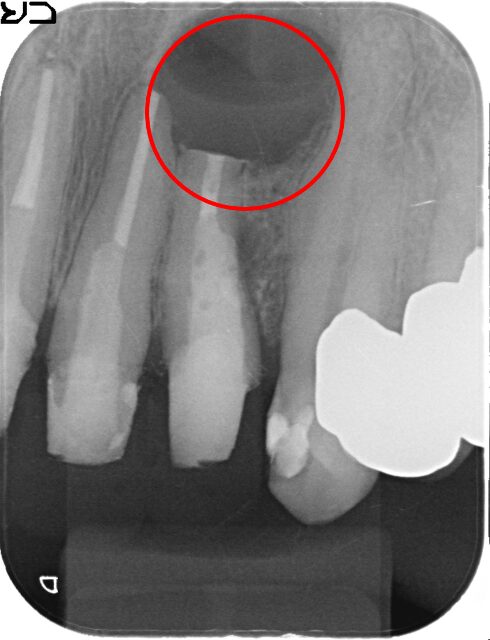

初診時

-

治療後

1年後

主訴

前歯の歯ぐきが腫れた。

治療の概要

根管治療では治らない歯に対して、根の先端を切除しそこから特殊な器具で穴をあけ、MTAという材料を充填し封鎖をはかりました。

1年後のレントゲンでは、根尖の病変がなくなり、骨ができています。